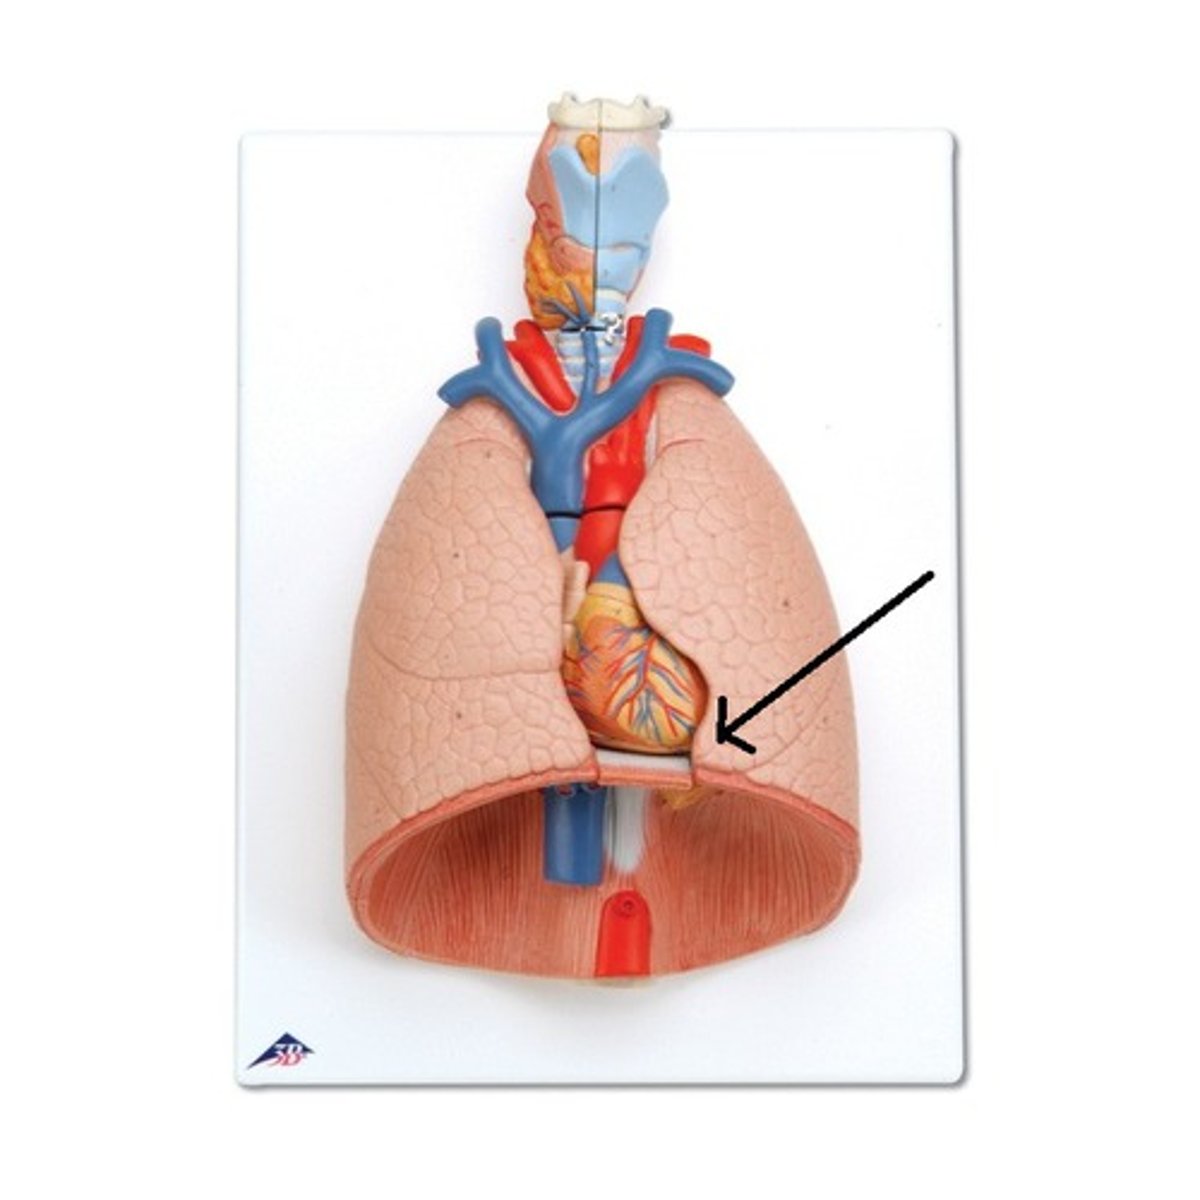

hilum

cardiac notch

a concave space on the left lung in which the heart lies